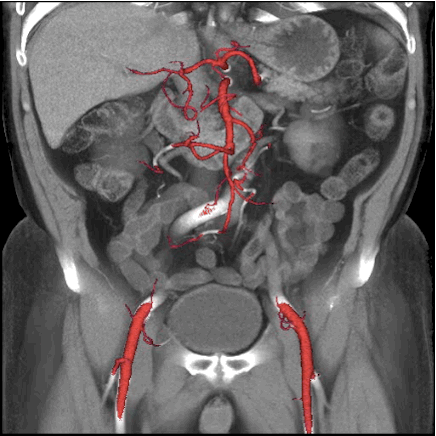

三是无限制一站式全身多部位血管联合成像

根据临床需要,很多患者需要做多部位的扫描,该CT独有的自由组合一站式联合扫描技术,实现不同扫描模式的快速切换,患者只需注射1次造影剂即可快速完成全方位联合扫描。常规情况下,患者需要分开几次预约扫描,而Revolution CT可以通过无限制的自由切换技术,实现扫描联合全身血管(包括头颈和下肢)同时扫描成像,可以帮助临床一次性解决所有问题,对患者没有任何禁忌,临床应用无限制。